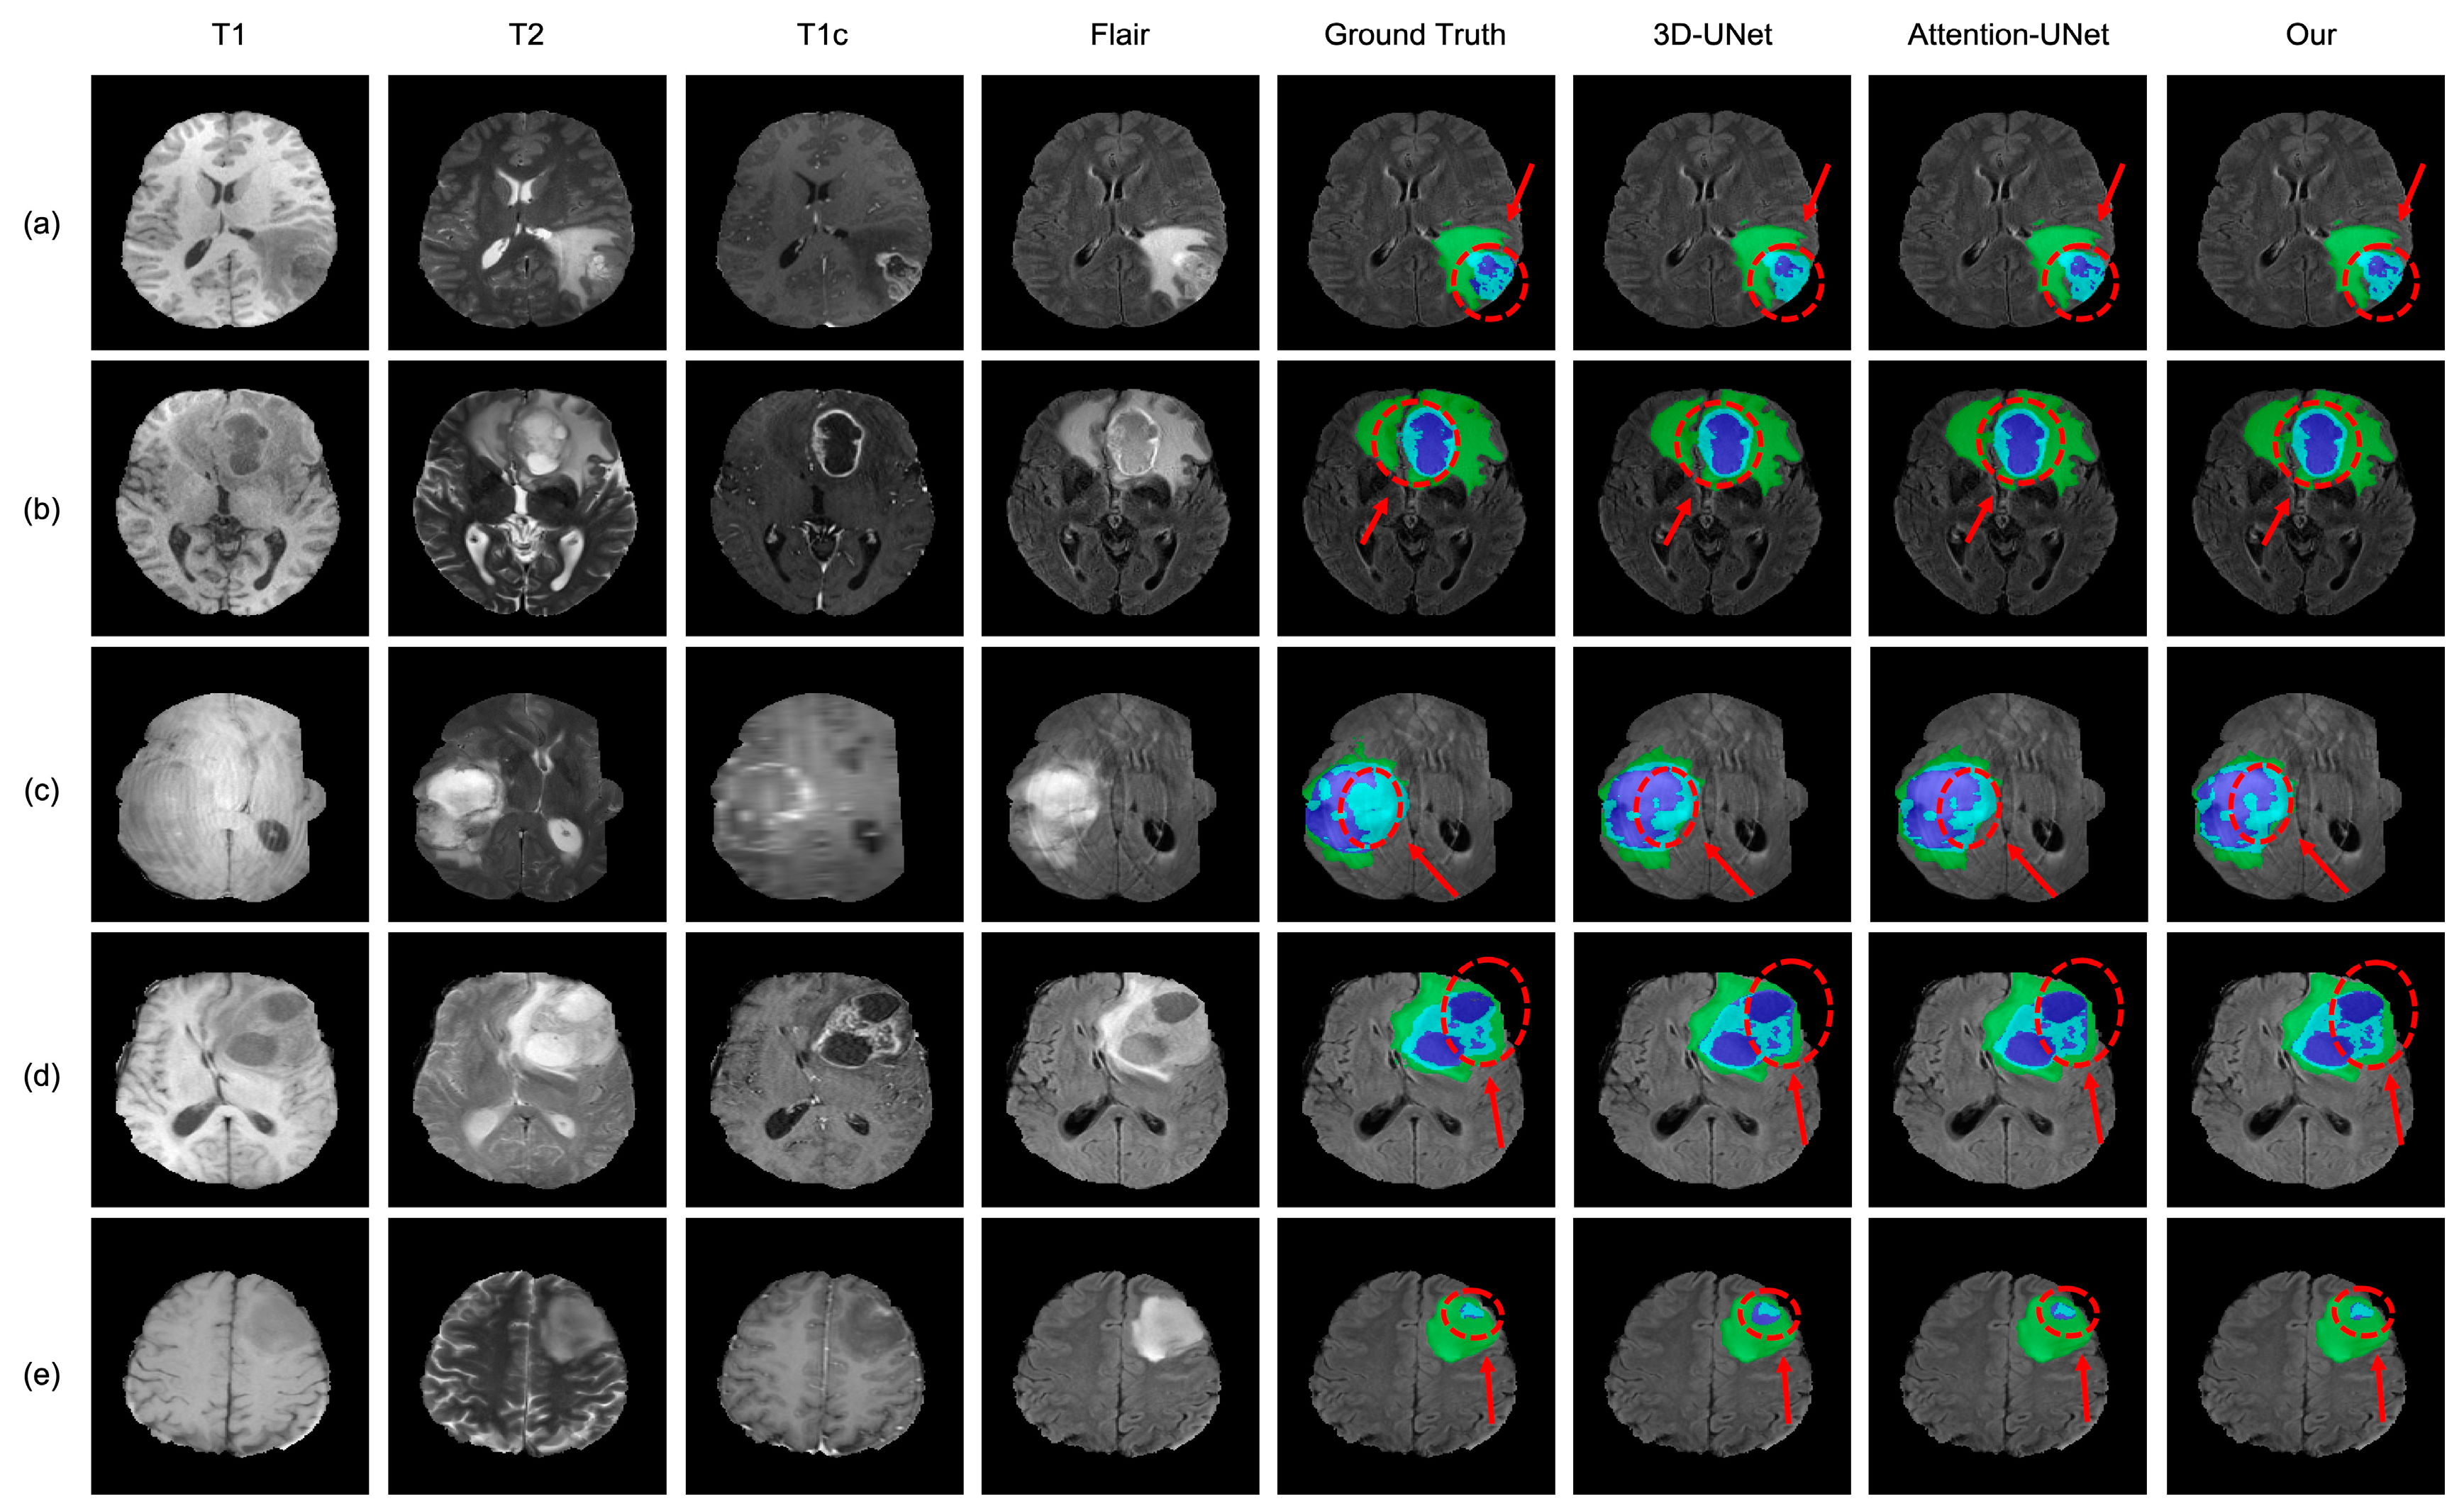

4.3. Analysis of the Bad Tumor Segmentation Results

| Cases | DSC | |||

|---|---|---|---|---|

| ET | TC | WT | AVG | |

| (a) BraTS2021_00493 | 0.885 | 0.924 | 0.270 | 0.693 |

| (b) BraTS2021_00494 | 0.964 | 0.990 | 0.730 | 0.895 |

| (c) BraTS2021_01666 | 0 | 0.738 | 0.916 | 0.551 |

| (d) BraTS2021_01179 | 1.000 | 0 | 0.769 | 0.590 |

| (e) BraTS2021_01293 | 0.541 | 0.929 | 0.874 | 0.781 |